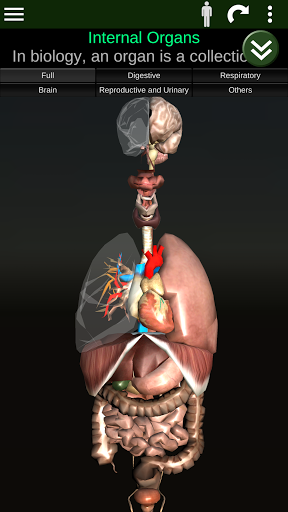

Toont een 3D-anatomisch model van de belangrijkste organen van het menselijk lichaam en een beschrijving van elk orgaan.

Wat zit er in de app?

* Spijsverteringsstelsel, inclusief de maag, dunne darm, dikke darm, en een animatie van dit systeem.

* Ademhalingssysteem, inclusief de luchtpijp, bronchiën, longen en een animatie van dit systeem.

* Voortplantingssysteem, dat de mannelijke en vrouwelijke voortplantingsorganen omvat.

* Hersenen, waaronder de hersenen, het cerebellum en de hersenstam vallen.

* Hart, dat de atria, ventrikels, aorta en een animatie van dit orgel omvat.

* Gemakkelijk te openen en te navigeren (zoom, 3D-rotatie).

* Verberg of toon informatie.

* Beschrijvingen van elk orgel.

Deze app is ontworpen als aanvulling op de studie van anatomie in verschillende onderwijs-, gezondheidszorg- en culturele omgevingen.